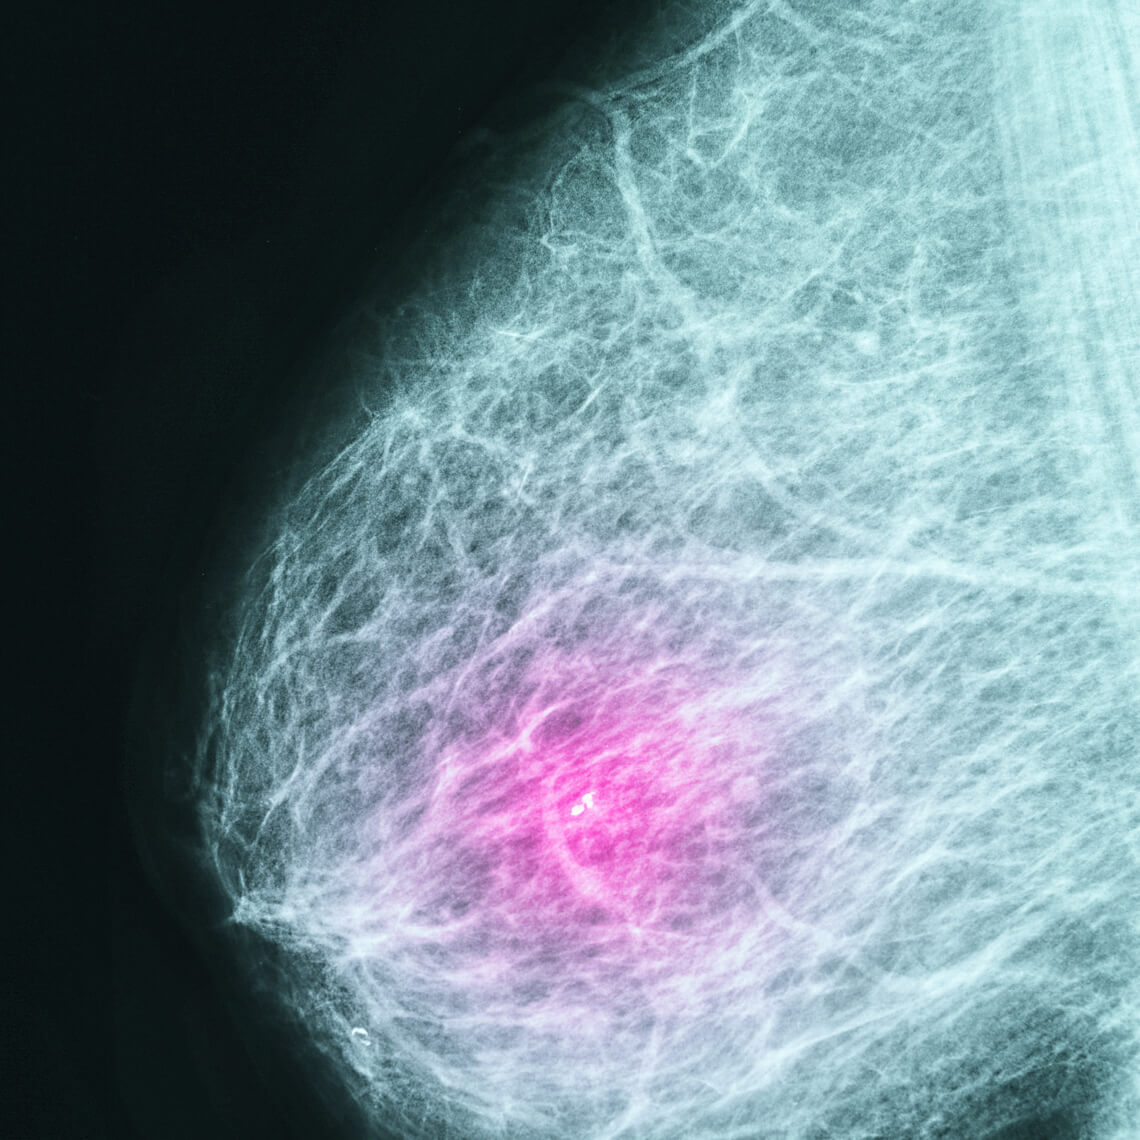

Breast Cancer Screening & Mammographic Follow-up Each month, our webinar series Mitigating Diagnostic Risks in Primary Care addresses a common diagnostic challenge facing clinicians. Register now to get the latest advice and insights for PCPs... |